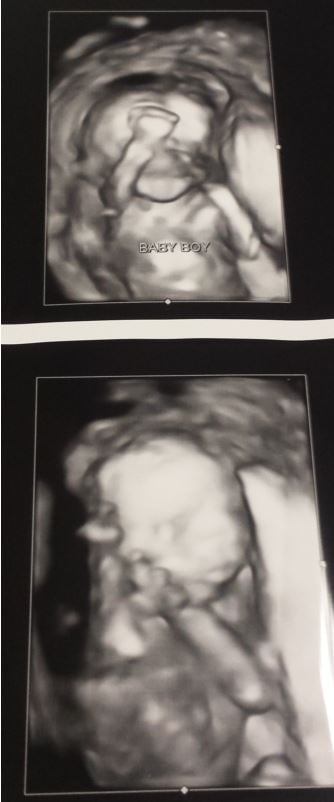

Here's our baby boy from our AS yesterday! I was 20w3d. MD said everything looks great and although they didn't change my due date, the report indicates a due date of 2/27 instead of 3/5. I'll take it! I was crying my eyes out when I saw that little face! We are in love!

Had my anatomy scan last week at 18 weeks. We are expecting a healthy little boy!

It's a BOY!!